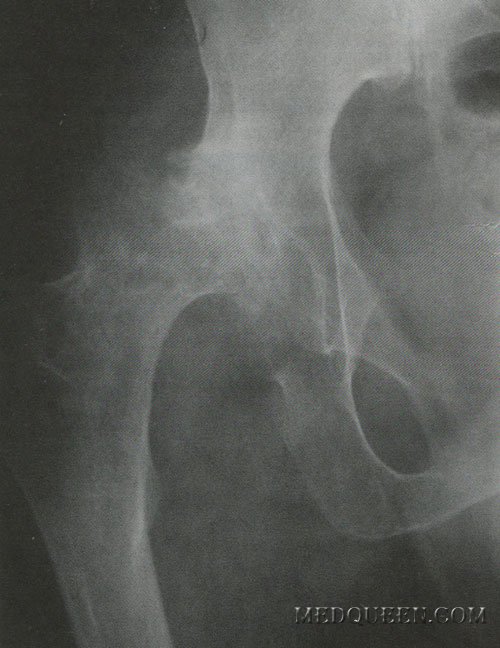

Комбинированное поражение костей таза у больного гемофилией А

У больного отмечены неоднократные кровотечения в суставы, а также кровотечения после незначительных травм. Комплексное поражение суставов нижних конечностей с анкилозированием диагностировано в 6-летнем возрасте, в тоже время была проведена хирургическая репозиция суставов. С 10 до 19 лет заболевание имело стабильное легкое течение. Ухудшение состояния (повышение частоты гемартрозов, которые появлялись спонтанно и сопровождались стабильным ухудшением функции суставов с выраженными общими воспалительными процессами) отмечено в 19 лет. учитывая этот фактор к заместительной терапии были назначены селективные ингибиторы ЦОГ-2 и глюкокортикостероиды. Данная терапия способствовала снижению выраженности симптомов воспаления, но через год пациент начал жаловаться на боль в костях, особенно в бедренных и тазовых. Результаты исследования показали остеопороз, при этом были назначены препараты кальцитонина, бисфосфонаты, но остеопоротические изменения костей продолжали прогрессировать, появились признаки двустороннего коксартроза.

У данного пациента многочисленные кровотечения в хрящ спровоцировали трофическое поражение костей, а терапия глюкокортикостероидами усилила катаболические процессы в костной ткани. Повторные кровотечения сформировали так называемый замкнутый круг патологического поражения и привели к выраженной деструкции тазовых костей и тазобедренного сустава (см. фото).